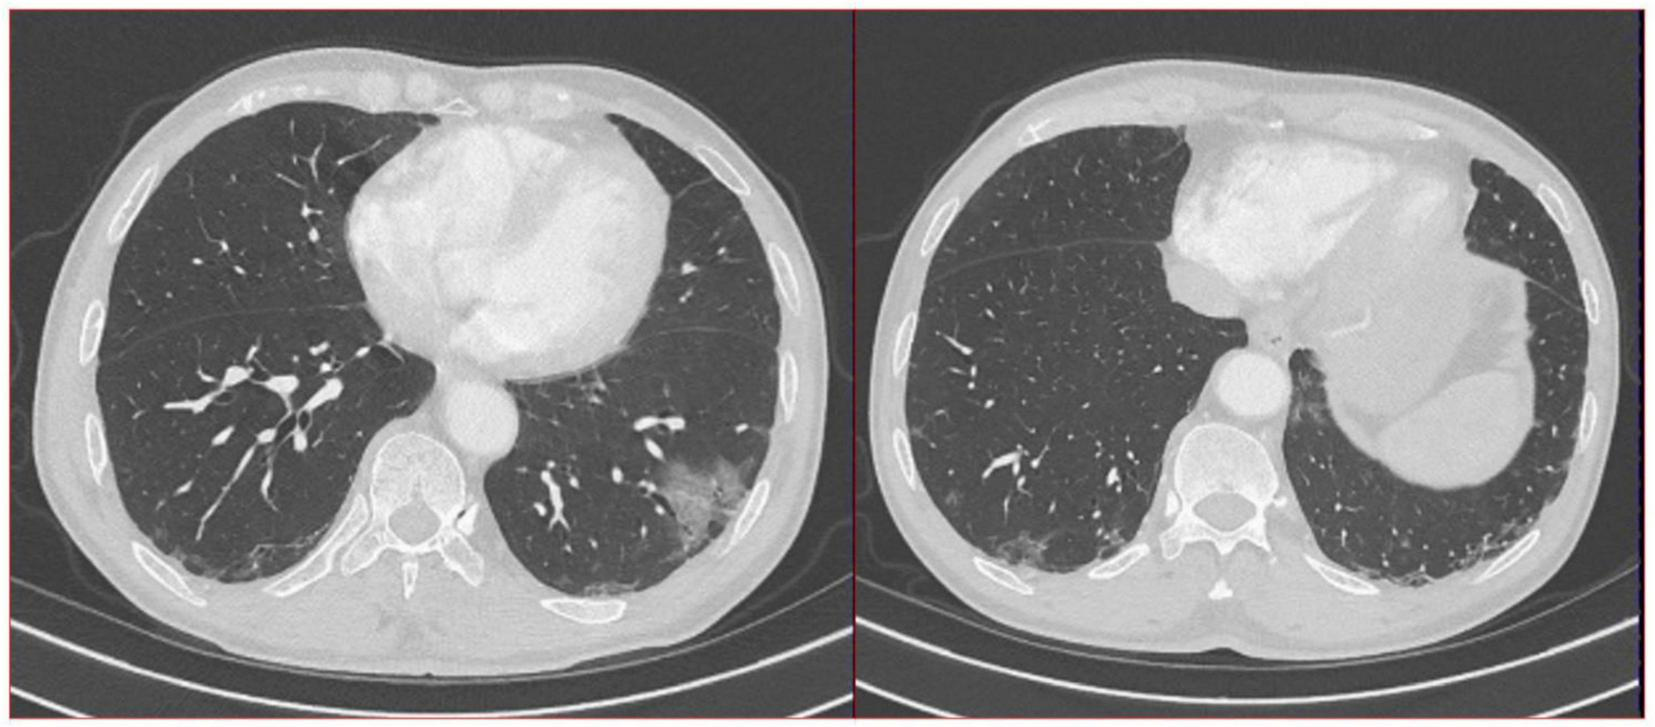

A 69 years-old male patient was hospitalized with lung nodules that had been present for the past 3 years. The patient was found to have small ground-glass opacities in both lungs on chest CT during a screening process for COVID-19 3 years ago (see Figure 1). One lesion in the lower lobe of the left lung was slightly larger, measuring about 0.5 × 0.4 cm, and had an irregular shape. The patient had a temperature of 36.6°C, a respiratory rate of 14 breaths per minute, and a heart rate of 62 beats per minute. The patient and his companion denied that he had asthma, chronic obstructive pulmonary disease, or gastroesophageal reflux disease. He recently denied having a fever, low-grade fever, obvious night sweats, diarrhea, skin-related abnormalities, or edema in his lower extremities. The patient has been smoking for more than 50 years and has not quit, with a daily average of 15 cigarettes. His professional occupation was not related to any special exposure or radiation exposure, and he reported no alcohol consumption, illicit drug use, or recent travel. The patient has no history of pet ownership or unclean sexual contact.

FIGURE 1

A total of 16-slice computerized tomography images of the chest at initial diagnosis period and in the subsequent 2 years of annual chest computed tomography (CT) re-examination of the patient.

The doctors suggested that the patient undergo percutaneous lung biopsy, but the patient refused. So, the patient was recommended a CT reexamination within 1 year. In the subsequent 2 years of annual chest CT reexamination, the imaging changes of both lung lesions were still not significant (see Figure 1). These imaging features did not reveal air bronchogram, and interlobular fissure bulging. However, in the third year of re-examination, chest CT showed that the lesion in the patient’s left lung was significantly larger than before, measuring approximately 3.2 × 3.1 cm. It appears that there are blood vessels running through it, and there is a burr sign (see Figure 2). 18F-FDG PET/CT was performed to identify the nature of lung lesions (see Figure 3). From the images, we can observe that the ground-glass opacities were diffusely distributed in both lungs, especially in the lower lobes of the left lung. The FDG uptake values varied, with a standard uptake value (SUVmax) range of 6.4–24.3, while the SUVmax was 3.7. Which was greater than the SUV value of 2.5 that could be diagnosed as lung cancer. There were no obvious enlarged lymph nodes in the lung hilum or mediastinum.